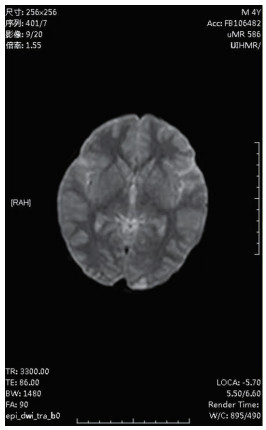

| 图 2 2月22日颅脑MRI |

图 1为颅内弥漫脑实质肿胀,脑沟脑回显示不清,脑室受压,部分脑沟内可见高密度影,右侧小脑幕密度增高。中线结构居中。副鼻窦内见软组织密度影。图 2为大脑皮层、小脑及脑干形态肿胀,呈稍长T2信号影,有类似束带征。图 3为后颅窝去骨辨减压+小脑部分切除术后复查: 脑疝征象明显好转。